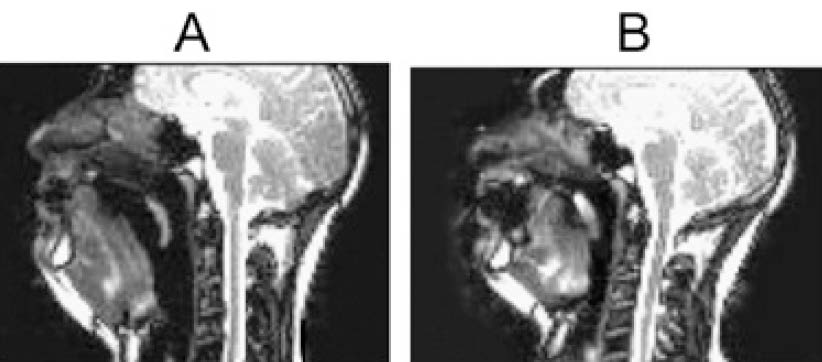

Figure 2. Degree of pharyngeal dysfunction at different levels of partial NMB8

Given that elderly have altered pharyngeal function which is associated with increased risk of aspiration, Cedborg et al (2014) evaluated the effects of partial NMB on pharyngeal function, coordination of breathing and swallowing, and airway protection in healthy individuals older than 65 years (n = 17). The results revealed that pharyngeal dysfunction increased significantly at TOF ratios 0.70 and 0.80 to 67% and 71%, respectively, compared with 37% at control recordings (n = 6, Figure 2), and swallowing showed a more severe degree of dysfunction during partial NMB8. The results complied with the illustration by Eikermann et al (2012) that minimal retroglossal upper airway diameter increased markedly during forced inspiration without NMB, whereas the increase was attenuated in partial NMB (Figure 3)9. These findings suggested that partial NMB would increase incidence of pharyngeal dysfunction and hence impair the ability to protect the airway.

Figure 3. Minimum retroglossal upper airway diameter during forced inspiration (A) before NMB and (B) at TOF = 0.809